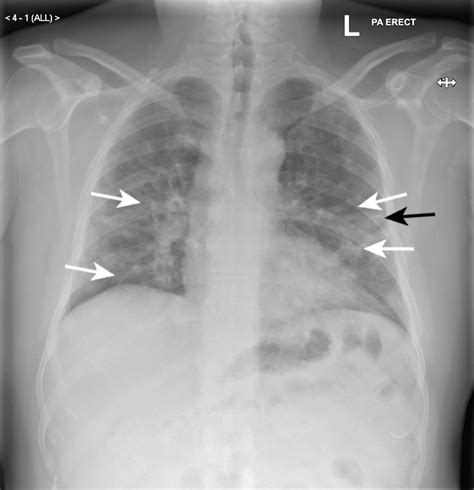

Healthy lungs appear mostly black on an X-ray because they are filled with air. When pneumonia is present, the areas of the lung affected by the infection appear as opaque, white, or cloudy patches. This phenomenon is known as consolidation. It occurs because the air in the alveoli has been displaced by fluid, inflammatory cells, or debris, which blocks the passage of X-rays.

Radiologists look for specific patterns of these opacities to better understand the nature of the infection:

• Lobar Pneumonia: This appears as a distinct area of consolidation restricted to one lobe of the lung. It is often associated with bacterial infections.

• Bronchopneumonia: This presents as patchy, diffuse opacities scattered throughout both lungs, rather than being confined to one area.

• Interstitial Pneumonia: Often caused by viral infections, this shows up as fine, lace-like markings or reticular patterns rather than dense consolidation.